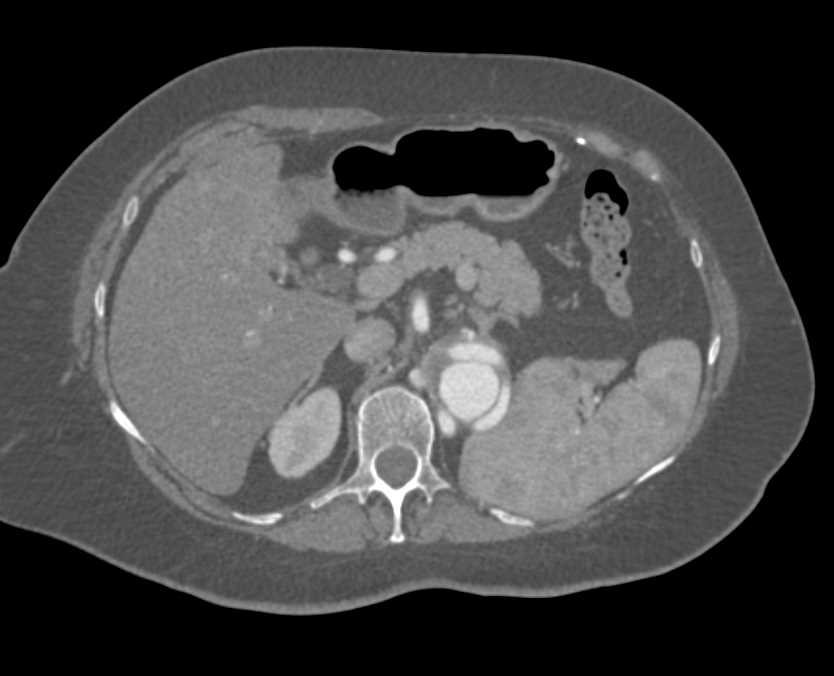

Post Aortic Valve Replacement (AVR) with Dilated Coronary Arteries at Reimplantation Sites